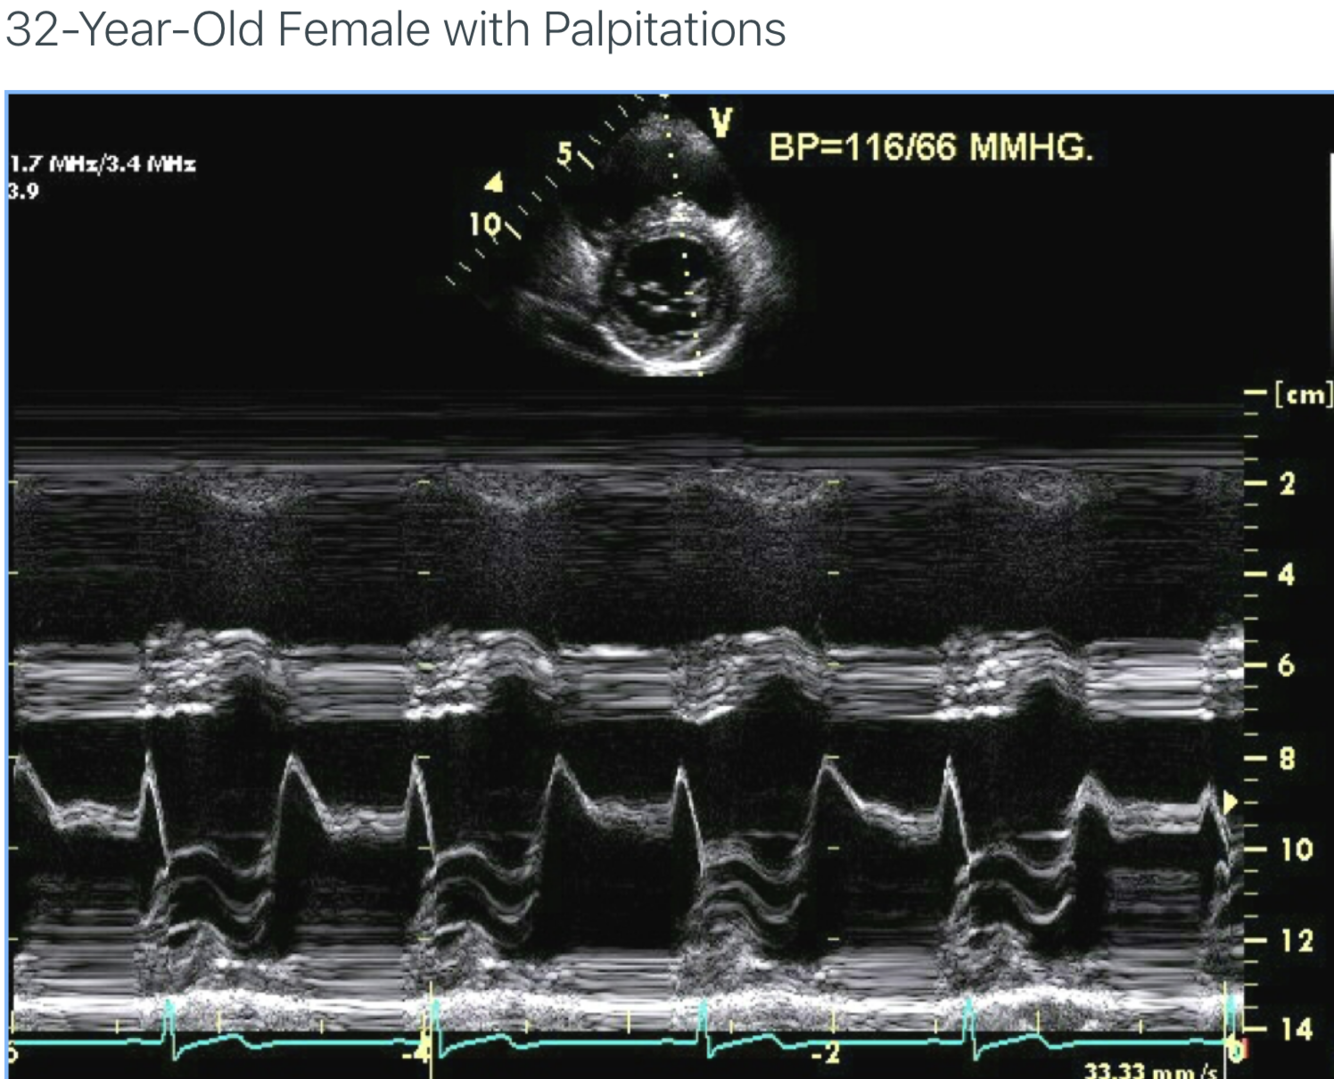

Describe the findings: